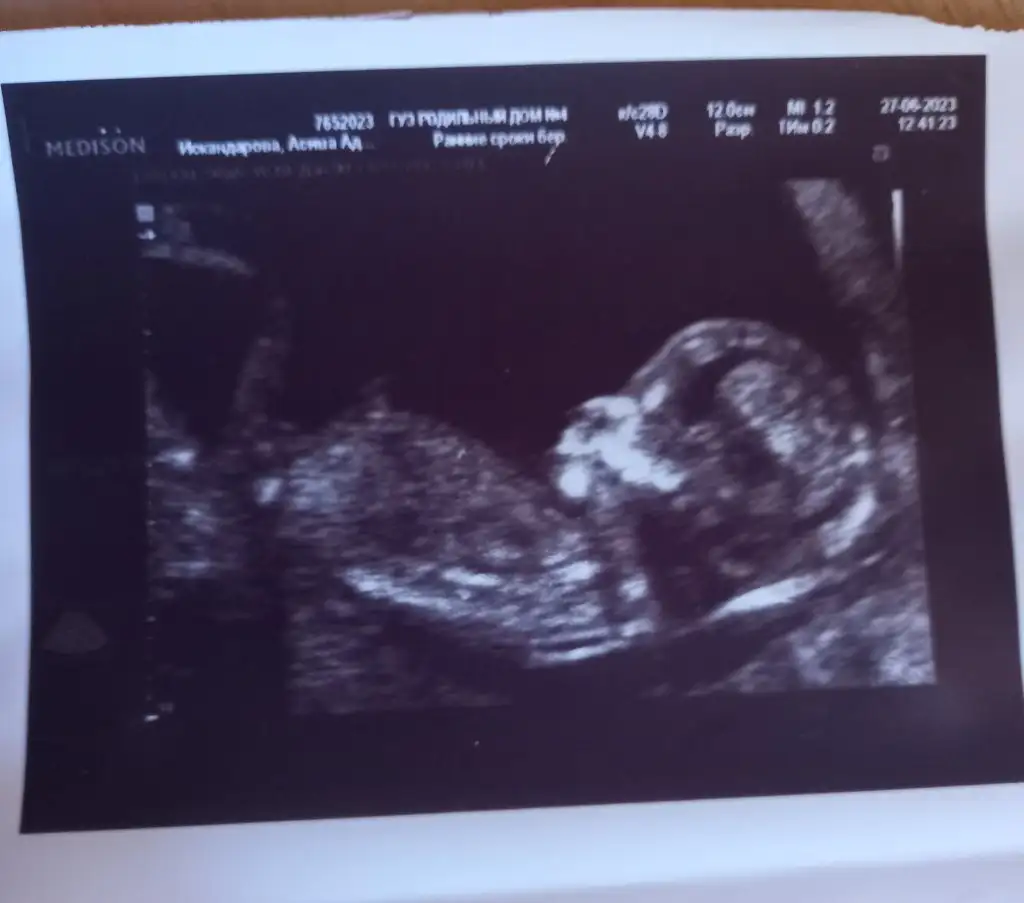

Bana da tahminde bulunur musunuz 13 haftalık olduk doktor erkeğe benziyor ama 16 haftalıkken belli olur dedi

Eklentiler

• 70a505eb-346f-40f9-80a3-992b3cccffce.webp

41,6 KB · Görüntüleme: 137